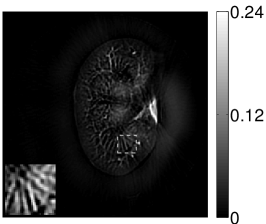

VI-E Results: kidney phantom

The images and EIRs reconstructed by use of the VP algorithm that was based on the 2D imaging model that neglected the SIR are shown in Figures 15 and 16. The latter figure contains results corresponding to different values for the regularization parameter . From Fig. 15, it can be observed that use of the conventional iterative method that utilized the measured EIR resulted in distortions and loss of details in the reconstructed images. Use of the VP algorithm improved the contrast and the details in the reconstructed images (Fig. 15(c) and 16(a)). Furthermore, the images reconstructed by use of the VP algorithm had a more uniform background.

In Figure 17, the results corresponding to use of the 3D imaging model that incorporated SIR effects are shown. The EIR estimated by the VP algorithm is also shown. In Figure 18, images and EIRs reconstructed by use of the VP algorithm with different regularization parameters values are shown.

Similar to the case described above where the transducer SIR was neglected, these results reveal that use of the VP algorithm can produce images with a cleaner background and enhanced spatial resolution than yielded by use of a conventional iterative algorithm that employed the measured EIR. For example, detailed information regarding the vessels near the organ’s periphery was better preserved by the VP algorithm than by the conventional iterative algorithm. These images corroborate our assertion that the VP algorithm can significantly reduce the artifacts and distortions in the reconstructed image. It is also worth pointing out that, unlike the numerical phantom studies, the artifacts and distortions in the images may be caused not only by the inaccurate EIR but also by other factors, such as neglecting acoustic heterogeneities and the variation of the EIRs among the elements of the transducer array. In such cases, the EIR estimated by the VP algorithm represents an effective system impulse response that minimizes the inconsistency between the measured data and the imaging model.